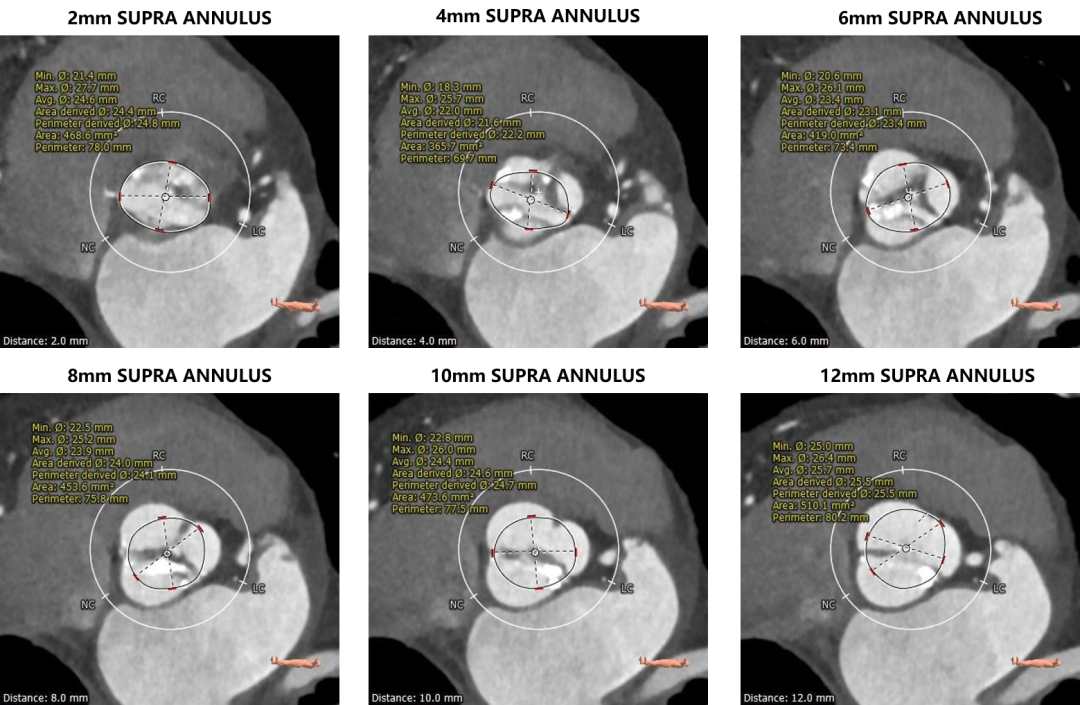

瓣环上测量

无锡明慈心血管病医院杨光院长团队在手术前对患者进行整体评估讨论,并在手术前进行手术模拟。本例手术最大的难点在于Type 1型二叶式主动脉瓣,钙化严重且分布不均且严重纤维增厚,不对称的解剖形态给瓣膜尺寸选择和释放带来了一定的挑战,钙化分布欠均匀及Type 1型二叶瓣椭圆的开口容易造成瓣膜贴壁不充分从而产生一定的瓣周漏风险,所以术中对于瓣膜的控制和及时调整显得非常重要。

手术策略:右侧股动脉为主入路,左侧辅助入路。选用20mm球囊行预扩张,预扩角度为左冠切线位(LAO 28° CRA 1°)。预装AV26瓣膜,由于左右重合体位太大,瓣膜释放体位采用无冠窦最低法,调整至(LAO 4° CAU 27°),释放深度控制在2-4mm。